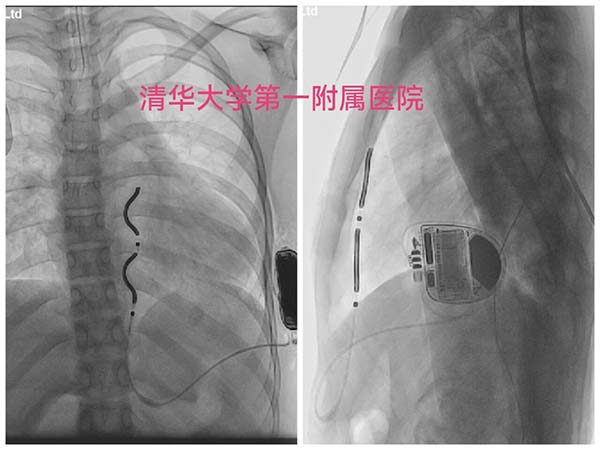

心脏中心小儿科EV-ICD首植成功

2025年11月5日17:00,小然在护士及家人陪伴下送入导管室,李小梅教授团队严阵以待,并邀请李学斌教授担任手术指导。麻醉科主治医师任倩倩为小然气管插管,平稳麻醉后,术者与助手均身着重达30斤的铅衣,李小梅教授开始摆放标准体位、消毒、铺巾,保证术区视野及术区清洁无菌;画体表标记线、做切口、分离组织、送电极、打隧道、做囊袋、固定……张仪副主任医师从旁协助,李学斌教授悉心指导,一切均有条不紊地进行。过程听起来似乎很轻松,其实稍有不慎就面临穿破心包、胸膜的风险。

当诱颤并除颤1次成功,无影灯下,李小梅教授与李学斌教授眼神里那属于匠人的锐利渐渐隐去,转而浮上一丝如释重负的疲惫以及深深的欣慰……

此次EV-ICD的成功植入是清华大学附属医疗系统的首次植入,也是国内首批。EV-ICD因其置于血管外、兼具ATP及停搏后起搏功能且体积小而独具优势,能够更好地惠及患儿。